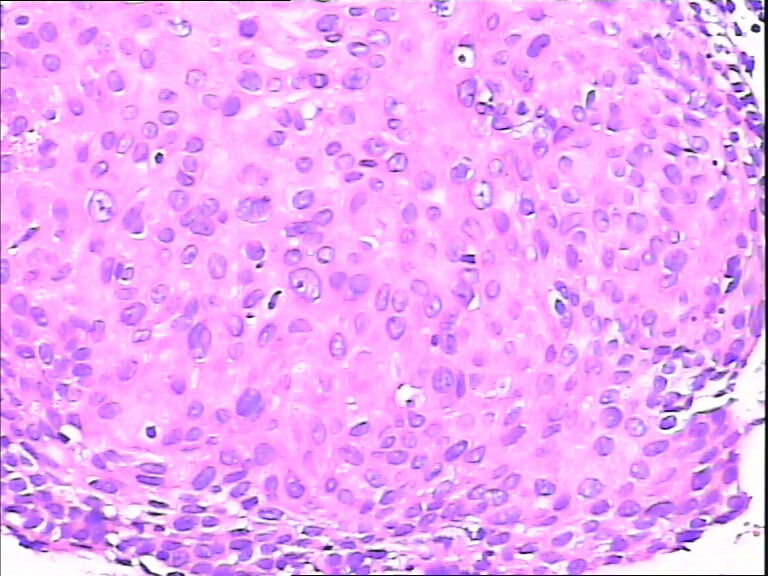

45y,触血,宫颈多点活检。